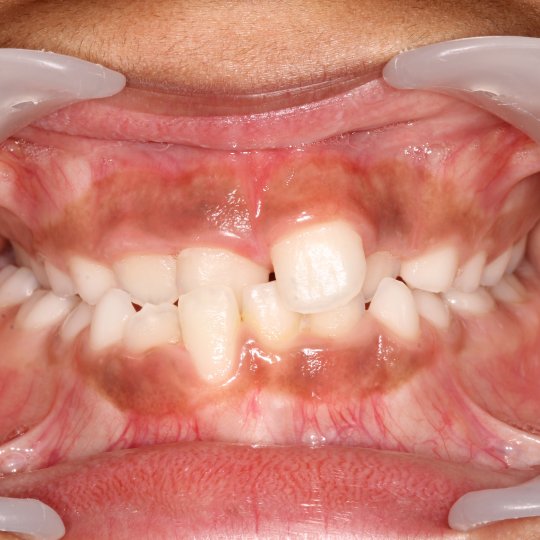

- Assimetrias na erupção dentária (foto 5)